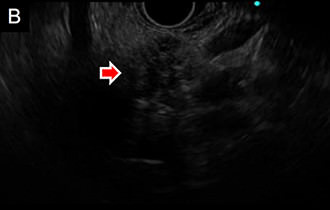

図3 超音波内視鏡像画像

体外からの超音波では描出不能な胆道・膵臓の疾患の詳細な描出が可能です。

A. 膵癌を疑う病変を認め、針生検を行い確診を得ました (↓)。

B. 血管との関係が明瞭に描出できます。

• B.内視鏡エコーによる膵腫瘤像